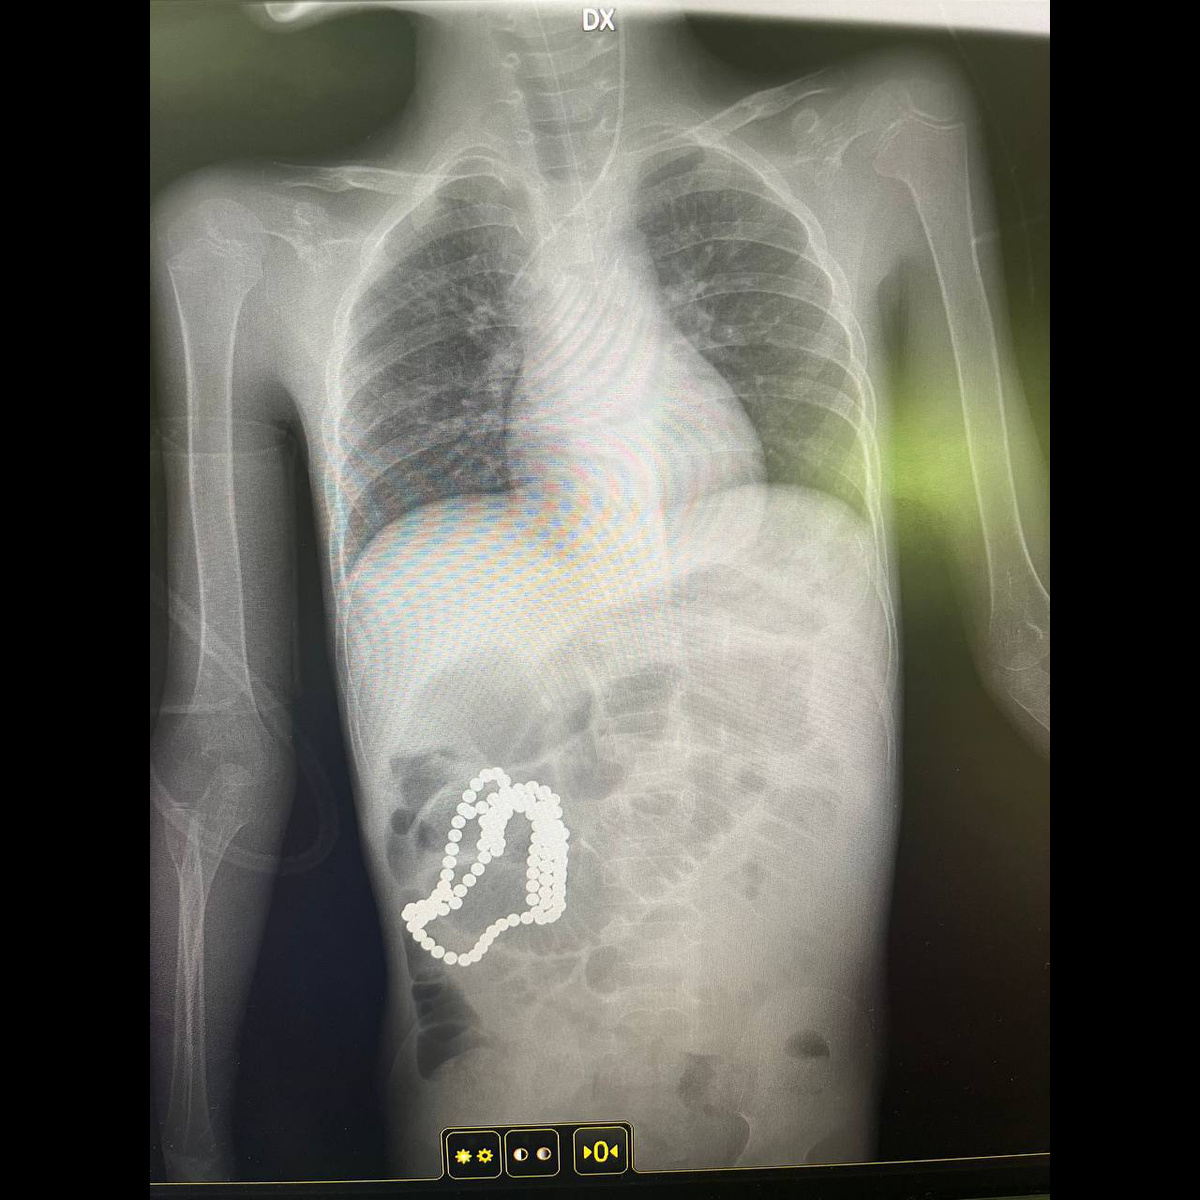

Осмотр в приёмном покое выявил признаки кишечной непроходимости. Рентгеновский снимок брюшной полости показал нечто неожиданное: в кишечнике девочки виднелись мелкие круглые объекты. Родители подтвердили, что среди игрушек есть конструктор из маленьких магнитных шариков. Никто не видел, как Полина их проглотила, играя без присмотра.

Если в больницу поступает ребёнок с симптомами острой боли и подозрением на инородное тело, первым делом ему сделают рентгеновский снимок. Магниты — это металлические объекты, и они хорошо видны на рентгене. При этом сразу можно определить их количество и расположение. Иногда врачи проводят дополнительные исследования, чтобы понять, не начался ли воспалительный процесс, нет ли осложнений: лабораторные анализы крови, мочи, кала, ультразвуковое исследование.